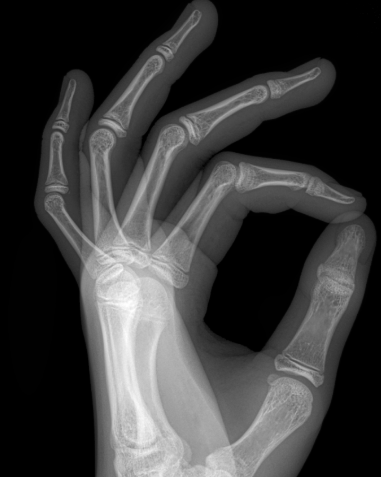

갑자기 손가락이 안구부러지더니 붓는거 있죠,,

병원에서는 손바닥쪽에서

뭔가 뼛조각 처럼 떨어져 나왔다고 하는데

반깁스를 해서 제자리로 돌아가게 붙여줘야 한다더라구요

이렇게 한달가량 깁스를 하게 되었고